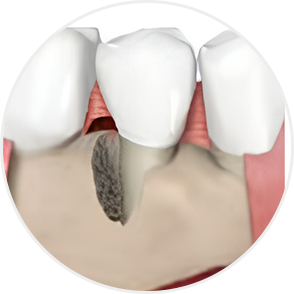

치아, 무조건 뽑지 않아도 됩니다

심한 치주질환으로 잇몸이 내려앉고 치조골이 흡수된 경우에도

엠도게인을 이용한 ‘잇몸재생술’을 통해

치아를 보존할 수 있습니다.

이 술식은 손상된 잇몸뼈와 주변 조직을 재생시키는 치료로,

엠도게인이라고 하는 잇몸조직을 재생시키는

주사를 사용하여 치아의 지지 구조를 다시 세워줍니다.

그 결과 치아를 뽑지 않고 기능과 건강을 회복할 수 있도록 돕습니다.